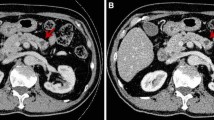

Optimal CNR single-energy value

As shown in Fig. 2, the images of 48 patients were analysed using single-energy spectra to obtain their respective CNR curves against keV values. The keV corresponding to the curve peak was the optimal CNR single-energy value. The average optimal CNR single-energy value for the 48 patients was 75.04 ± 1.24 keV, ranging from 73 to 78 keV.

CECT images show the presence of necrosis as single or multiple regions of nonenhancing pancreatic parenchyma in ANP patients [7]. Additionally, multislice CECT scans are beneficial for identifying the complications of AP due to its value in disease diagnosis and severity grading [21]. Recently, the advance of DECT with iodine quantification allows differentiation of normal pancreatic parenchyma from inflammatory pancreatic parenchyma and exerts superior sensitivity for diagnosing early AP compared to standard imaging methods [22]. Dual-energy spectral CT iodine substance analysis better detects the presence of pancreatic microcirculation injuries in AP and offers material decomposition image analysis for assessing the severity of AP [23]. DECT has applications for oncologic and nononcologic pancreatic imaging. It achieves dual-energy spectra scans by acquiring images with two different tube voltages (i.e., 80 and 140 kVp). Due to energy-dependent photoelectric effects and different K-edges for different elements, DECT can differentiate structures of similar densities and diverse elemental compositions (such as calcium and iodine) [24]. Contrast-enhanced dual-source and DECT scans at a low-energy (80 kVp) can address differences concerning attenuation between necrotic loci and normal pancreas, thereby improving CNR and subjective evaluation of necrosis [12]. In this study, we found the optimal single-energy value for CNR in 48 patients to be on average 75.04 ± 1.24 keV, ranging from 73 keV to 78 keV.